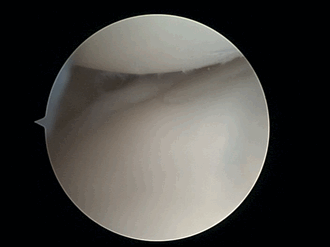

Боковой мениск расположен между бедренной костью (бедренная кость, вверху) и кость голени (большеберцовая кость ниже). Большеберцовая хрящ показывает трещину (кончик инструмента-задиры).

Артроскопия (также называемый артроскопический или же замочная скважина хирургия) является минимально инвазивный хирургическая процедура на совместный при котором обследование и иногда лечение повреждений проводится с использованием артроскоп, эндоскоп который вводится в сустав через небольшой разрез. Артроскопические процедуры можно проводить во время ACL реконструкция.